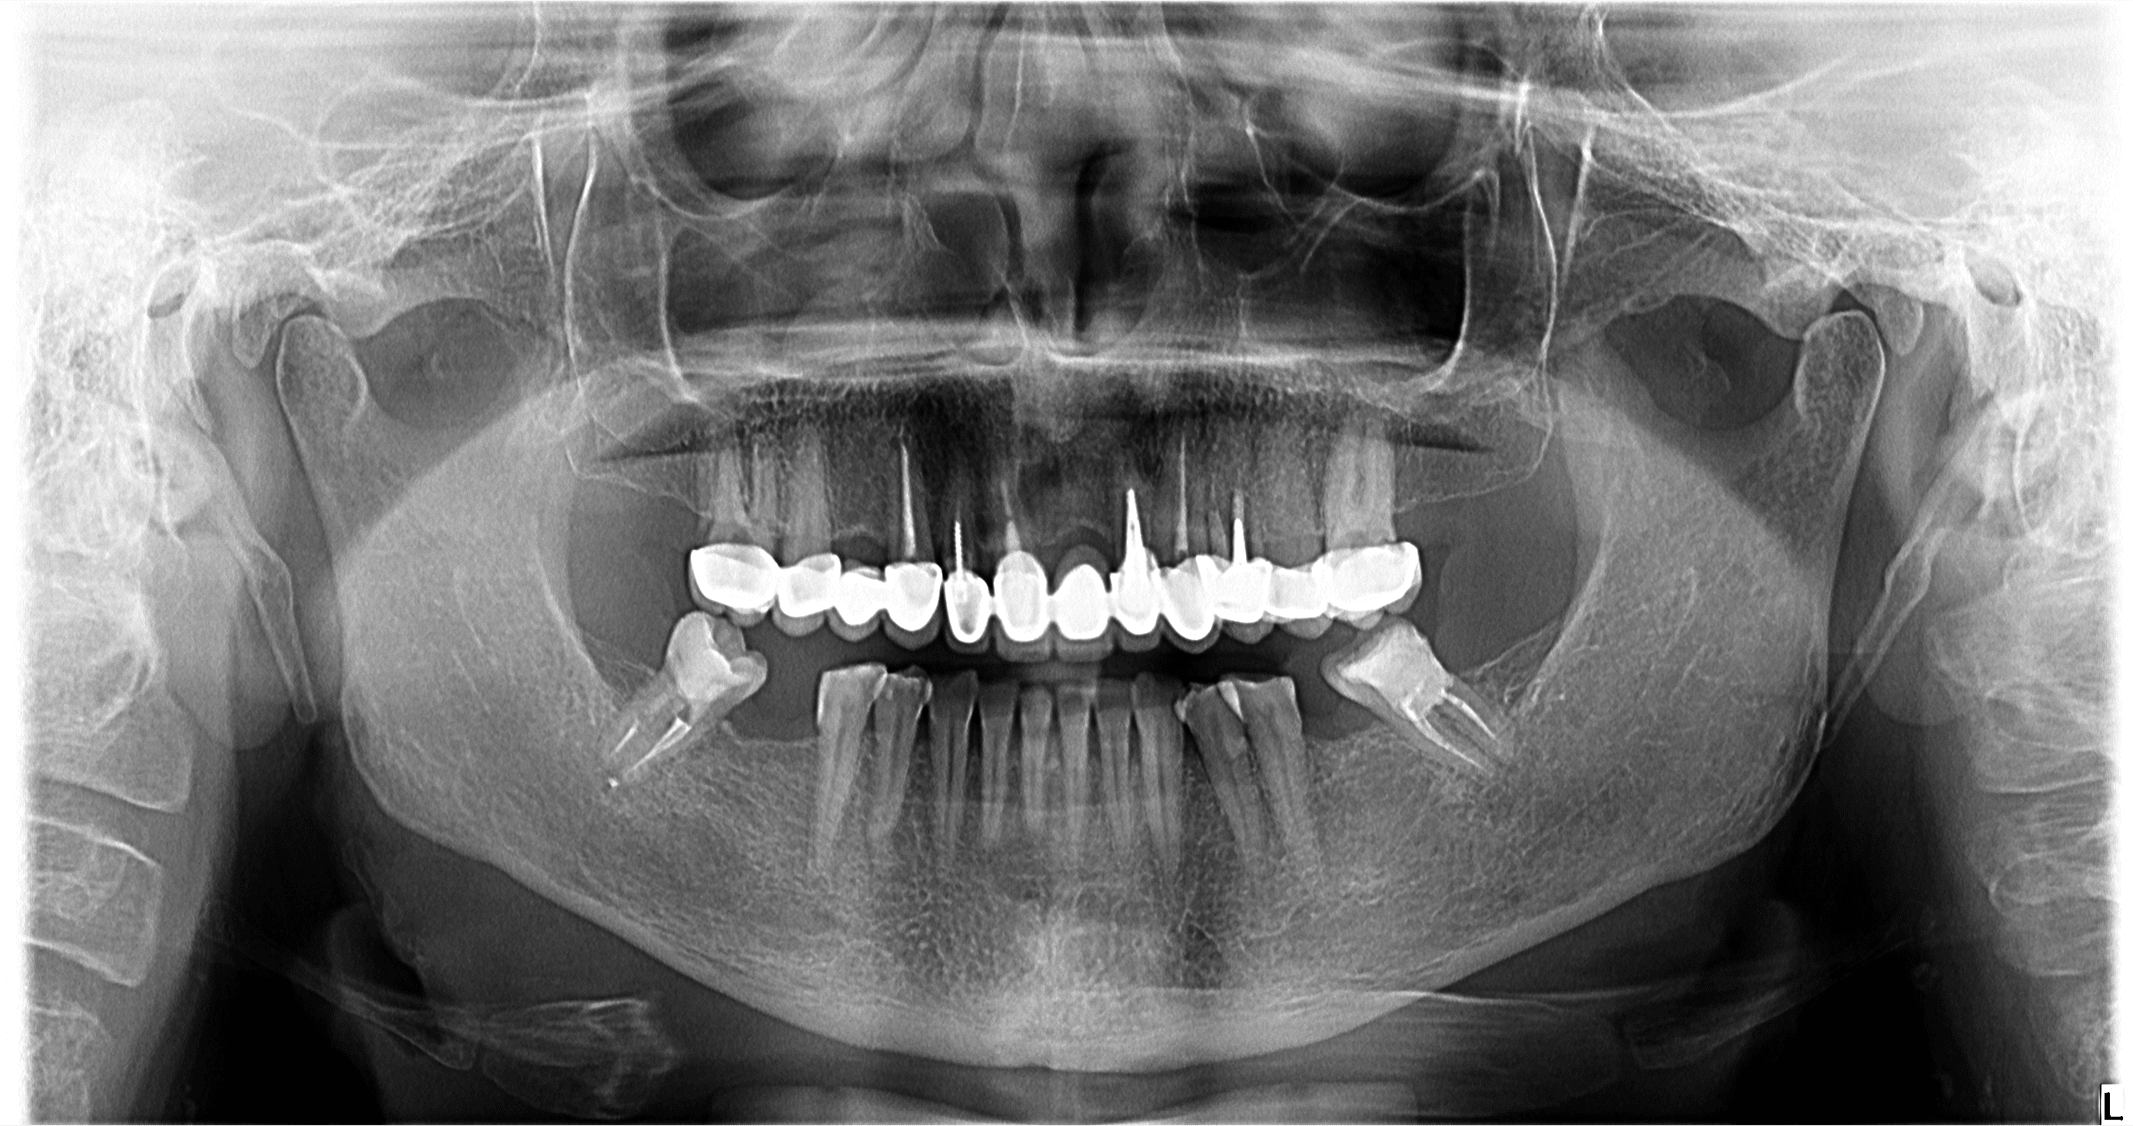

Pacienta se prezintă în clinică pentru refacerea lucrărilor dentare.

Implanturile vor fi inserate cu ghid chirurgical după 6 luni. Se vor insera implanturi în pozițiile 12, 22, 16, 36, 46.

S-a realizat scanarea digitală a arcadelor și ocluzia pacientului, iar împreună cu tehnicianul radiolog de la DigiRay, Dr. Eliza Drăgan a efectuat în software-ul 3Shape suprapunerea fișierului .stl al amprentei digitale peste fișierul .dcm de la CBCT. Medicul a planificat individual poziția și axul de inserție al fiecărui implant.